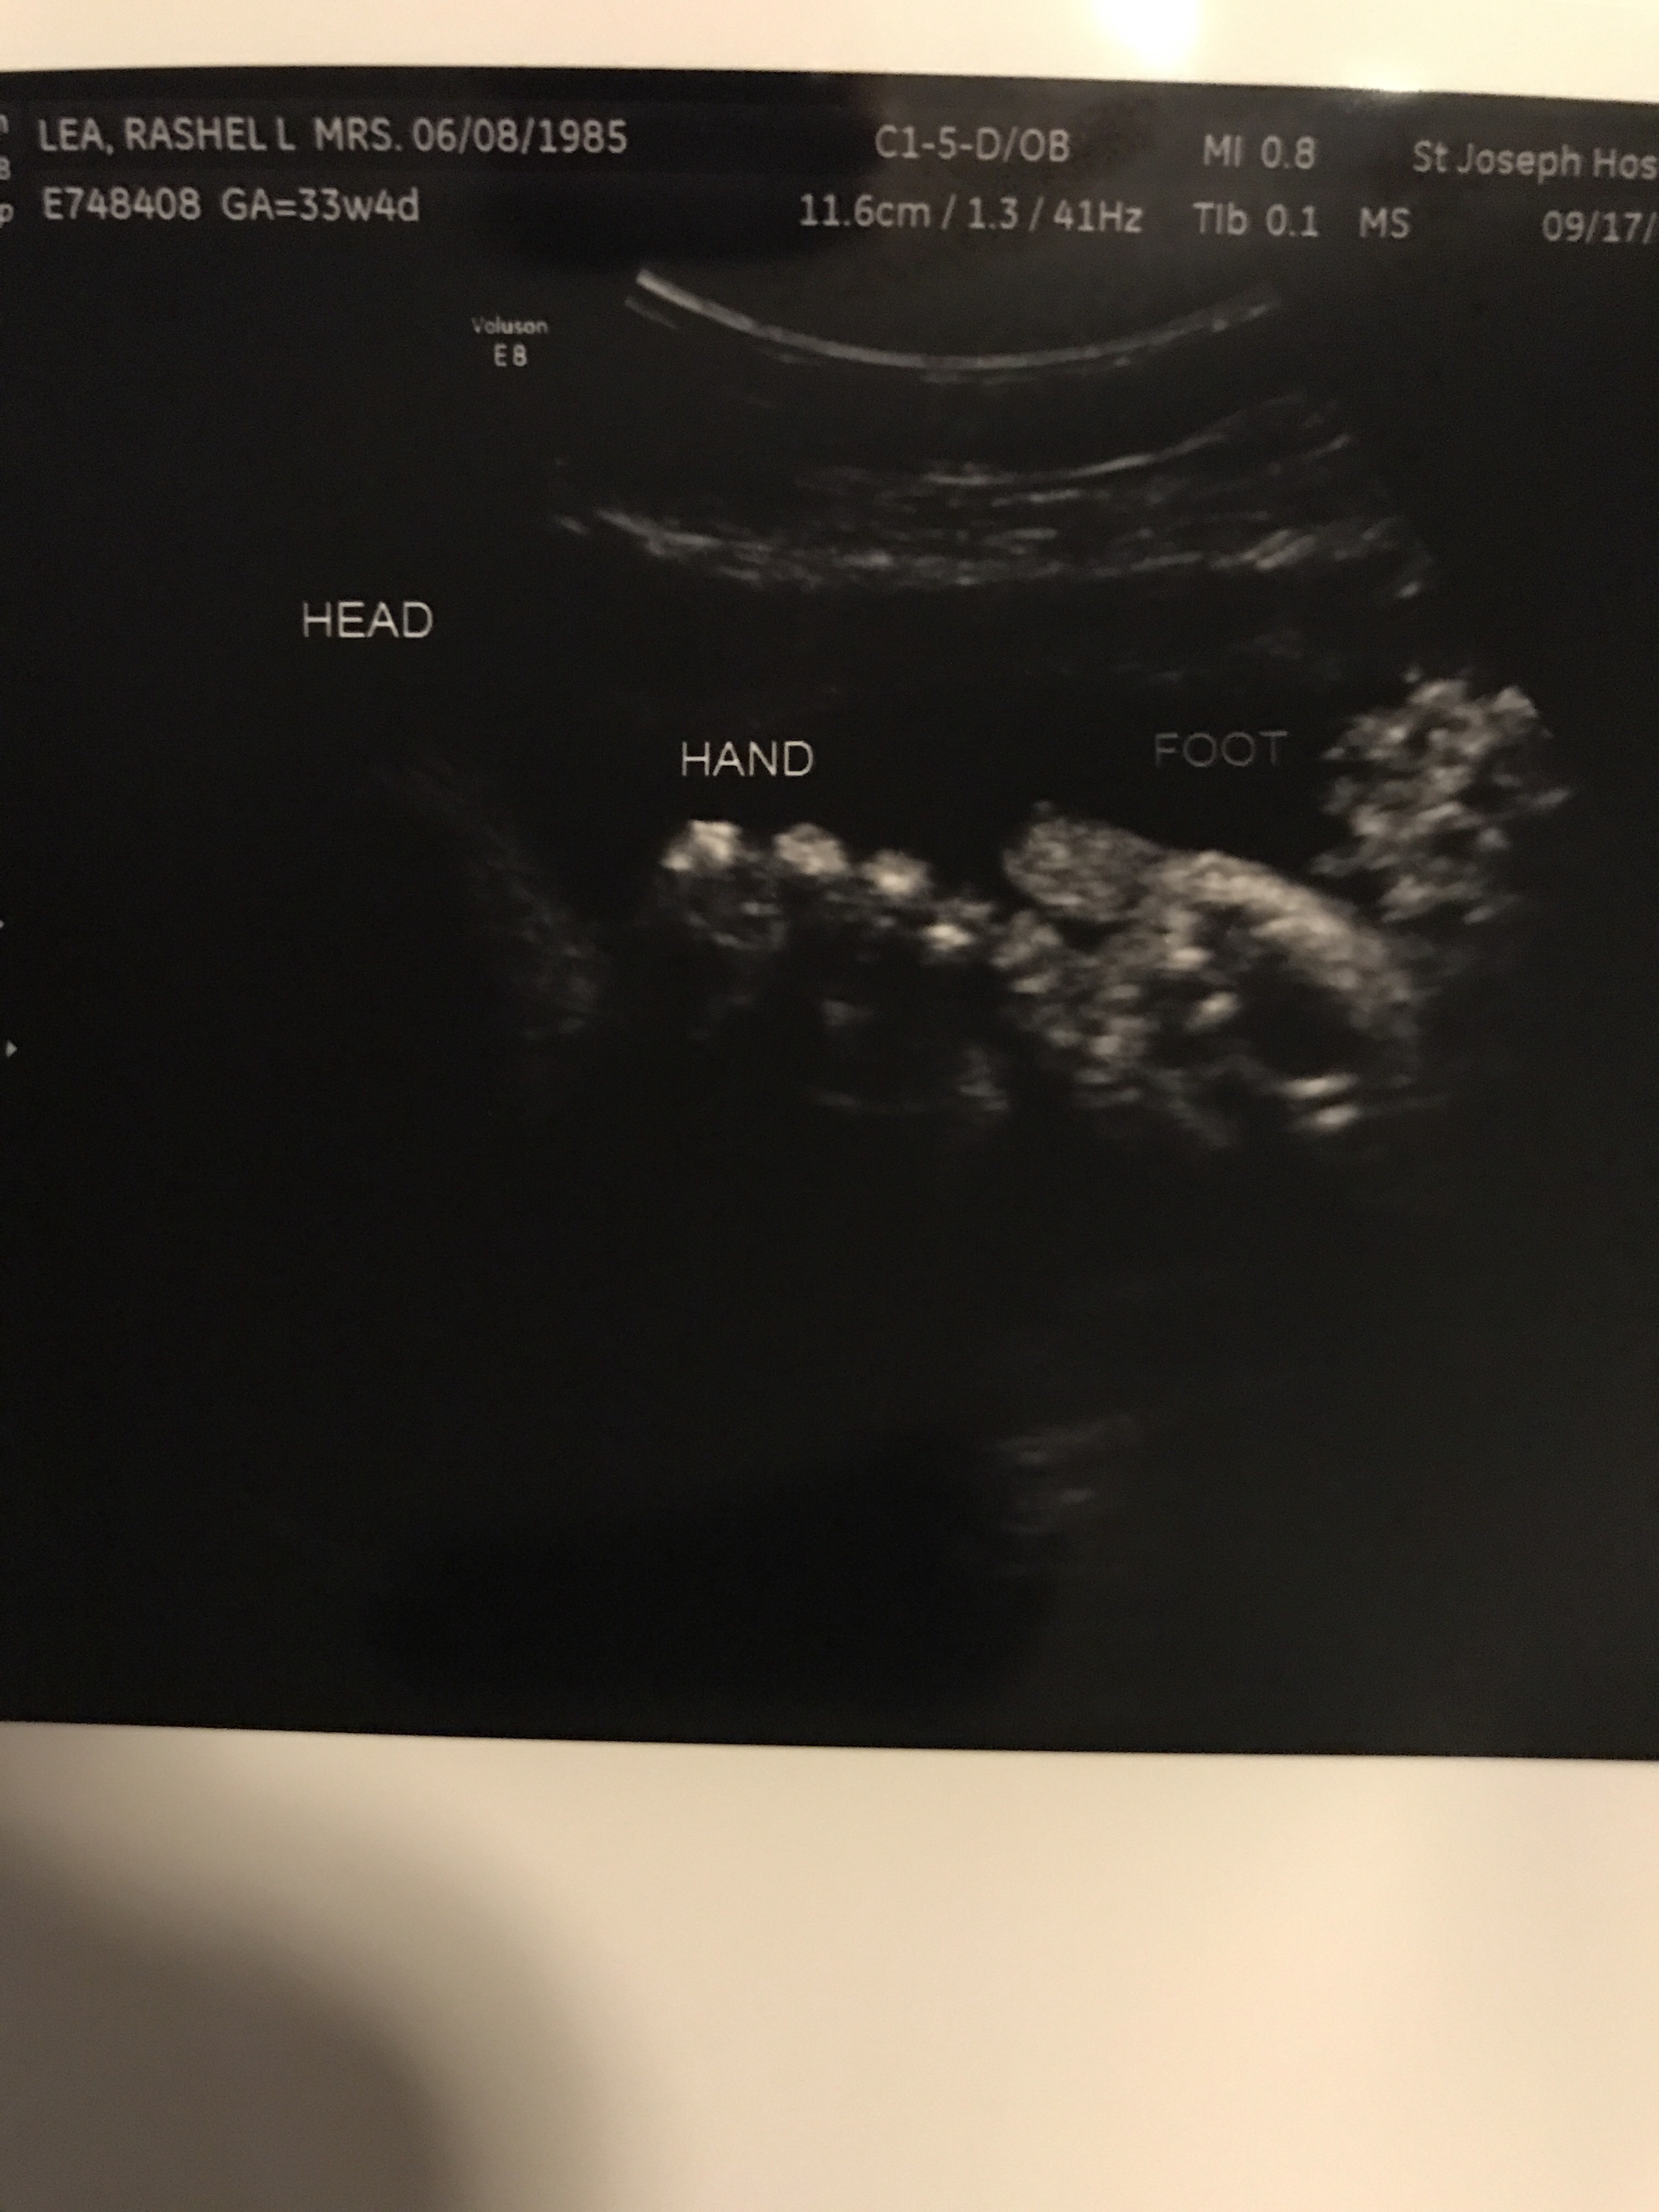

Things are going well. Baby B is enjoying life on the inside. He likes to kick and play often. We love our fun time together as long as it’s not in the middle of the night. Haha. I’m definitely getting more stretching ligaments if you have had them you know they are zero fun. If you haven’t let me try to explain. It’s basically like you move from any normal position and all the sudden it feels like someone has a huge sharp knife and they are stabbing you with it. Every time you try to move or adjust the knife is being twisted viciously. This happens always by surprise you never know when to expect the knife fight but let me tell you I always lose lol. I’m still eating all my ice! I love love LOVE crunching on ice. I’m definitely getting more round and I freaking love it! People can tell now so that’s great. I look super cute in clothes! Now out of clothes not so much… I have had a few Braxton-Hicks from time to time usually when I’m busy at work and not drinking enough water. I asked Dr. Google since it seemed a bit early and of course he said it’s normal when you have had a few pregnancy’s. I guess number 5 counts as a few! I also followed up with my real dr who also said yep it’s fine! I still feel super lucky I haven’t gained any weight yet and I feel great. Sometimes I get a bit winded and I can’t eat a ton but that’s all fine! Our next appointment I will be 28 weeks so it’s basically a all day appointment since I have to do my sugar test plus another ultrasound since baby B wasn’t very cooperative at the 20 week ultrasound. Then I’ll meet the dr and then get to go home. I’m not allowed to eat two hours before my test so when I leave I’m sure I’ll be starving! I wonder if it would be frowned upon if I ordered a pizza or something and delivered it to my dr office while I wait??? I sure hope my sugar test comes back good this time. Last time it was close so they made me do the long 3 hour test! Then we get to go see my Dr every two weeks! This pregnancy is flying by. I love and hate the end! I’m so happy and excited for J and K to get their sweet baby boy! Plus I’m so excited to give birth and see what he looks like! I just always feel a little sad that I won’t be pregnant anymore. I feel so incredibly blessed that his mommy and daddy picked me to help keep him safe until he is big enough to go home and live with them. I can’t begin to explain how humbling and special that is to me! Everyone loves to say what a incredible person I am, but really the incredible people are baby B’s parents! To put that kind of trust into anyone is incredible! I’m so happy out of all the people they could have picked they chose me. I also can’t help but be a bit jealous this sweet baby boy gets to go live by the ocean! What a lucky boy he is! Now let’s see what baby B is up to this week! Plus a few pics!